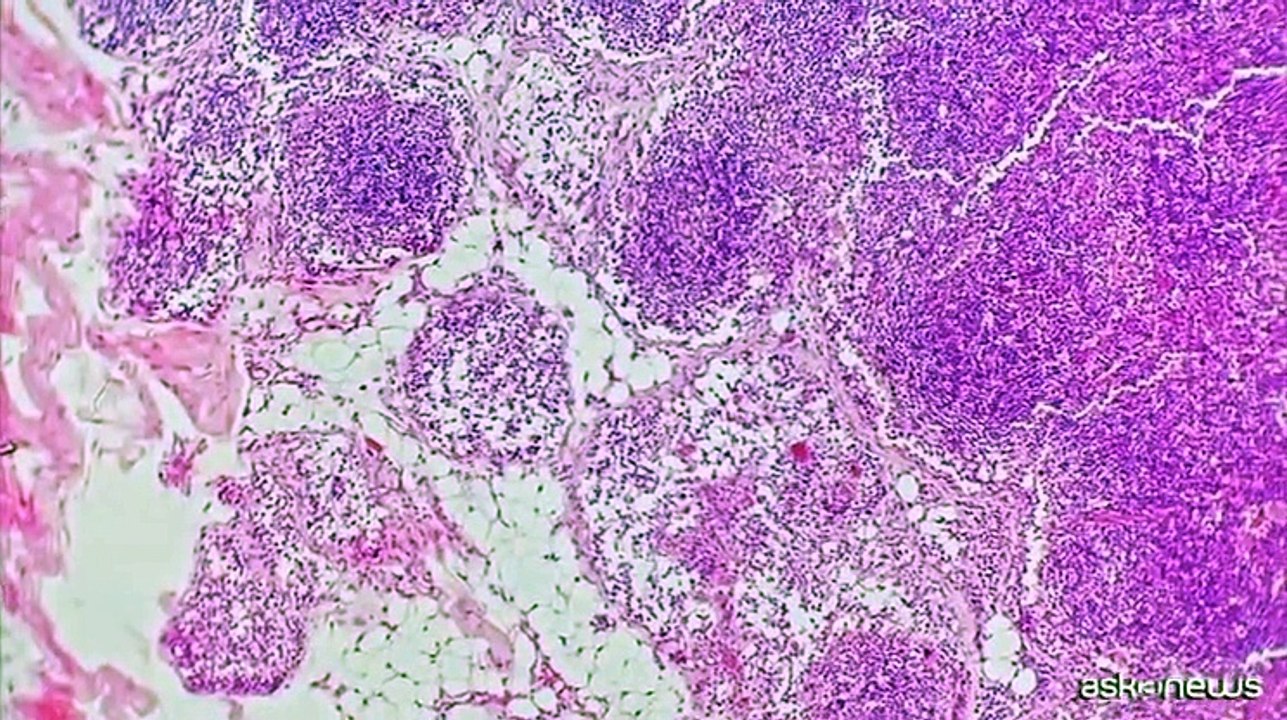

Linfoma follicolare, AIFA approva mosunetuzumab